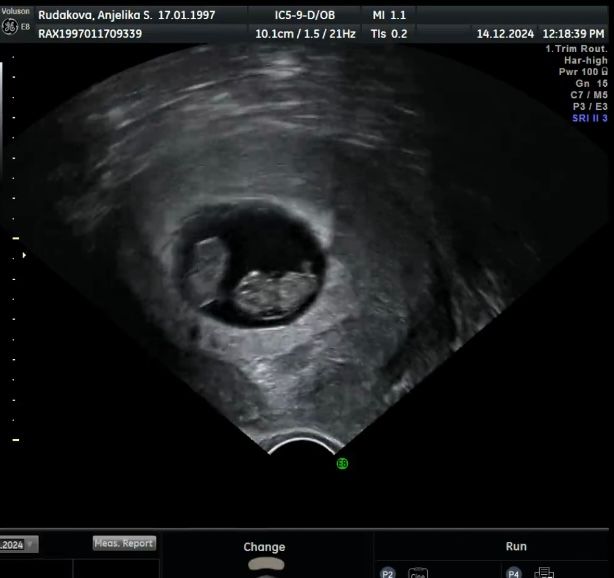

Подросли ) малыши по 2 см

Двойнята! Ничеси! Первый раз вижу узи двойни)

Маргарита, это близнецы)))двойня у каждого свой домик.А близнецы в одном домике живут.)))

Катюша Климова, коллега 😅👍 Перегородку не видать вроде. Не находили её вам?

Елена, перегородки нет пока :( мне кажется и не будет .. единственное они в оболочке каждый в своей . Моно ди короче

Анжелика Мяделец, при моно ди и должна быть перегородка. Но у меня её нашли только в 13 недель.

Елена, я вот надеялась что плаценты будет 2 . Но это не возможно да ?

Лика , при монохориальной одна плацента всегда. Совет 😁 если вам немного за 30, на скрининг лучше идти с готовым ниптом. Может повезёт, но могут риск поставить. Кровь при двойне неиформативна, но вам всё равно её будут учитывать. И обязательно сходить на хорошее узи во время скрининга и в 16 недель. Иногда и в ЖК бывают хорошие специалисты, но вот у меня (а это ближнее Подмосковье, на минуточку) большинство оказались некомпетентны: "а зачем это вам узи в 16 недель", "а шейку каждые две недели у нас никому не мерят". Есть конкретные рекомендации в случае моно двойни и лучше их соблюдать. Изучите и следите, компетентен ли врач, который вас ведёт, в этом вопросе.